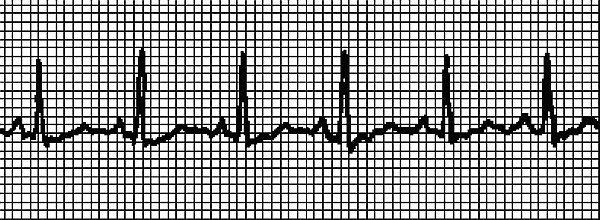

Что надо сделать до приезда врача и после снятия приступа Пароксизмальную тахикардию должен устранить врач. Если нам удастся справиться с приступом до приезда врача – замечательно! Но электрокардиограмма все же необходима, поскольку мы устраним только симптом, и ненадолго. Итак, действия при внезапной тахикардии таковы. • Прежде всего, надо успокоиться, не волноваться, поверить, что сердце надежно выдерживает кратковременную аритмию с ЧСС выше 200 единиц. И немедленно принять 40–50 капель корвалола, или корвалдина, или валокордина. • Несколько раз надавить на глазные яблоки четырьмя пальцами рук: надавливаем и отпускаем, надавливаем и отпускаем, и еще раз, и еще раз. • Медленно плавно и глубоко вдохнуть, затем на 30 секунд задержать дыхание, медленно и плавно выдохнуть. Как диагностируют тахикардию Если после снятия приступа больной решит поскорее забыть о случившемся – это неоправданная беспечность! Тахикардию надо диагностировать, то есть пройти осмотр у врача, сделать ЭКГ и суточный мониторинг по Холтеру (об этом исследовании читайте ниже, в разделе Возбудимость – еще одна функция сердца/Как уловить экстрасистолию ). Врач обязательно назначит клинический и биохимический анализы крови, анализ гормонов щитовидной железы, чтобы исключить или подтвердить «не сердечную» причину тахикардии. Возможно, понадобится пройти ультразвуковое исследование сердца. ЭКГ при тахикардии ... Для проведения электрокардиограммы не требуется никакой специальной подготовки. Но есть 2 рекомендации. 1. ЭКГ проводится после 15–20 минутного отдыха. Придя в поликлинику, не заходите сразу в диагностический кабинет, отдохните, чтобы на результатах кардиограммы не отразилась аритмия, связанная с ходьбой. 2. Перед исследованием не рекомендуется плотный прием пищи. Однако и натощак записывать ЭКГ не надо. На рис. 2 записан нормальный синусовый ритм, на рис. 3 ритм при синусовой тахикардии. ЭКГ записывали у одного и того же человека сначала в состоянии покоя, затем после нагрузки. Даже не имея медицинского образования, можно понять, что существенных изменений в работе сердца не произошло – только учащение сокращений. На рис. 4 записана несинусовая тахикардия. Водитель ритма смещен в предсердие. Если такая тахикардия легко устранится, то причина может быть не связана с болезнью сердца. Врач иногда снимает подобное состояние массажем! Это так называемый массаж каротидного синуса, который проводится в области сонной артерии (καρόω и означает «засыпать», по-гречески). Но без диагностики состояния, без ЭКГ «назначить» массаж нельзя, он не является безобидной процедурой и может нанести вред! Поэтому при пароксизмальной тахикардии ограничимся рекомендацией надавливать на глазные яблоки , которую мы уже приводили. При устойчивой предсердной аритмии можно заподозрить легочную недостаточность или инфаркт миокарда. ![]() Рис. 2. Синусовый ритм ![]()

Рис. 5 должен впечатлить тех, кто злоупотребляет алкоголем, антидепрессантами, много курит или забывает, что несколько чашечек кофе на фоне усталости – это сильнодействующее средство. Скрытая до времени болезнь сердца в сочетании с этими коварными пристрастиями приводит к желудочковой тахикардии , которая относится к аритмиям, вызванным нарушениемфункциивозбудимости (см. ниже Возбудимость – еще одна функция сердца ). Насколько далек такой сердечный ритм от нормального, заметит даже ребенок! Однако будем справедливы, и скажем, что в ряду причин, которые провоцируют желудочковую тахикардию, стоят также дефицит (или избыток) калия, длительное кислородное голодания по разным причинам, органические поражения сердца, длительный прием сердечных гликозидов и других антиаритмических средств, прием психотропных лекарственных средств.